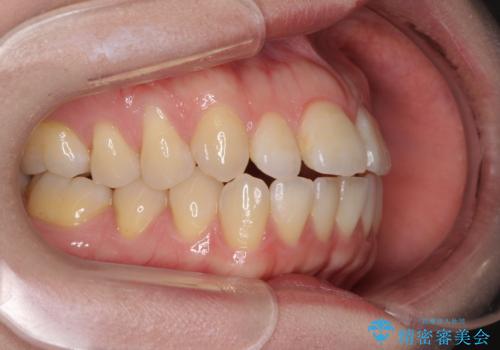

- 唇の閉じにくさを気にして来院された患者様です。

上下左右第一小臼歯4本を抜歯し、ワイヤー装置にて口元を引っ込めるよう矯正治療を行うこととしました。

骨格的に下顎がやや前方にあるため、横顔のシルエットが著しく変化することはありませんでしたが、口元はスッキリと引っ込み、唇が閉じやすくなりました。